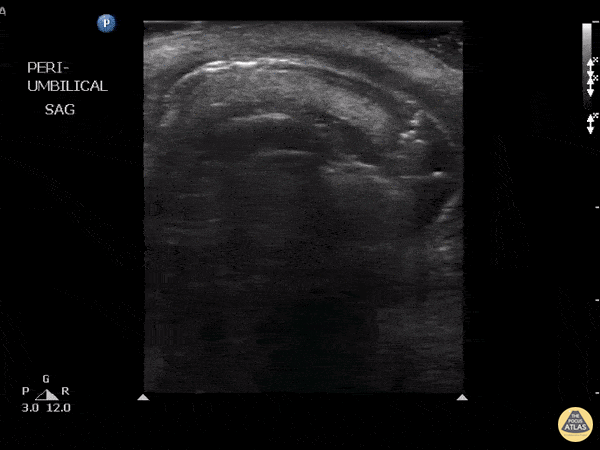

This patient presented with a known paraumbilical hernia however what should be noted here are is the lack of peristalsis as well as the presence of air in the within the wall of the bowel. These findings suggest that necrosis has resulted from strangulation of a hernia. Other findings with this diagnosis that could also be found include hyperechoic fat, fluid within the sac, thickening of the hernial sac, dilated bowel and edema within the walls. Image courtesy of Robert Jones DO, FACEP @RJonesSonoEM Director, Emergency Ultrasound; MetroHealth Medical Center; Professor, Case Western Reserve Medical School, Cleveland, OH View his original post here